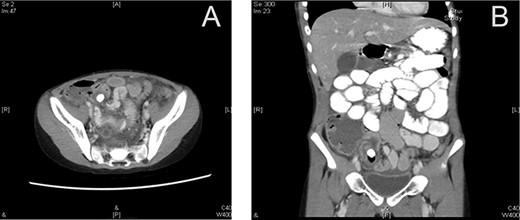

A CT cystography was performed, and it showed a vesicourachal diverticulum. The suprapubic drain that was placed intraoperatively was shown to be penetrating the diverticulum (Fig. 2). The urology department was consulted and the patient’s condition was discussed with his family. Management options were offered, including conservative management with Foley catheter placement and operative repair; the family opted for conservative management. The management included hourly monitoring of his urine output, antibiotic prophylaxis with intravenous cefuroxime 625 mg thrice a day and intravenous metronidazole 350 mg thrice a day, daily laboratory investigations (complete blood count, renal function tests and serum electrolytes), and a cystography performed after 7 days. The patient’s daily urine output is shown in Table1.

Multiple sagittal views showing the drain penetrating the urachus.